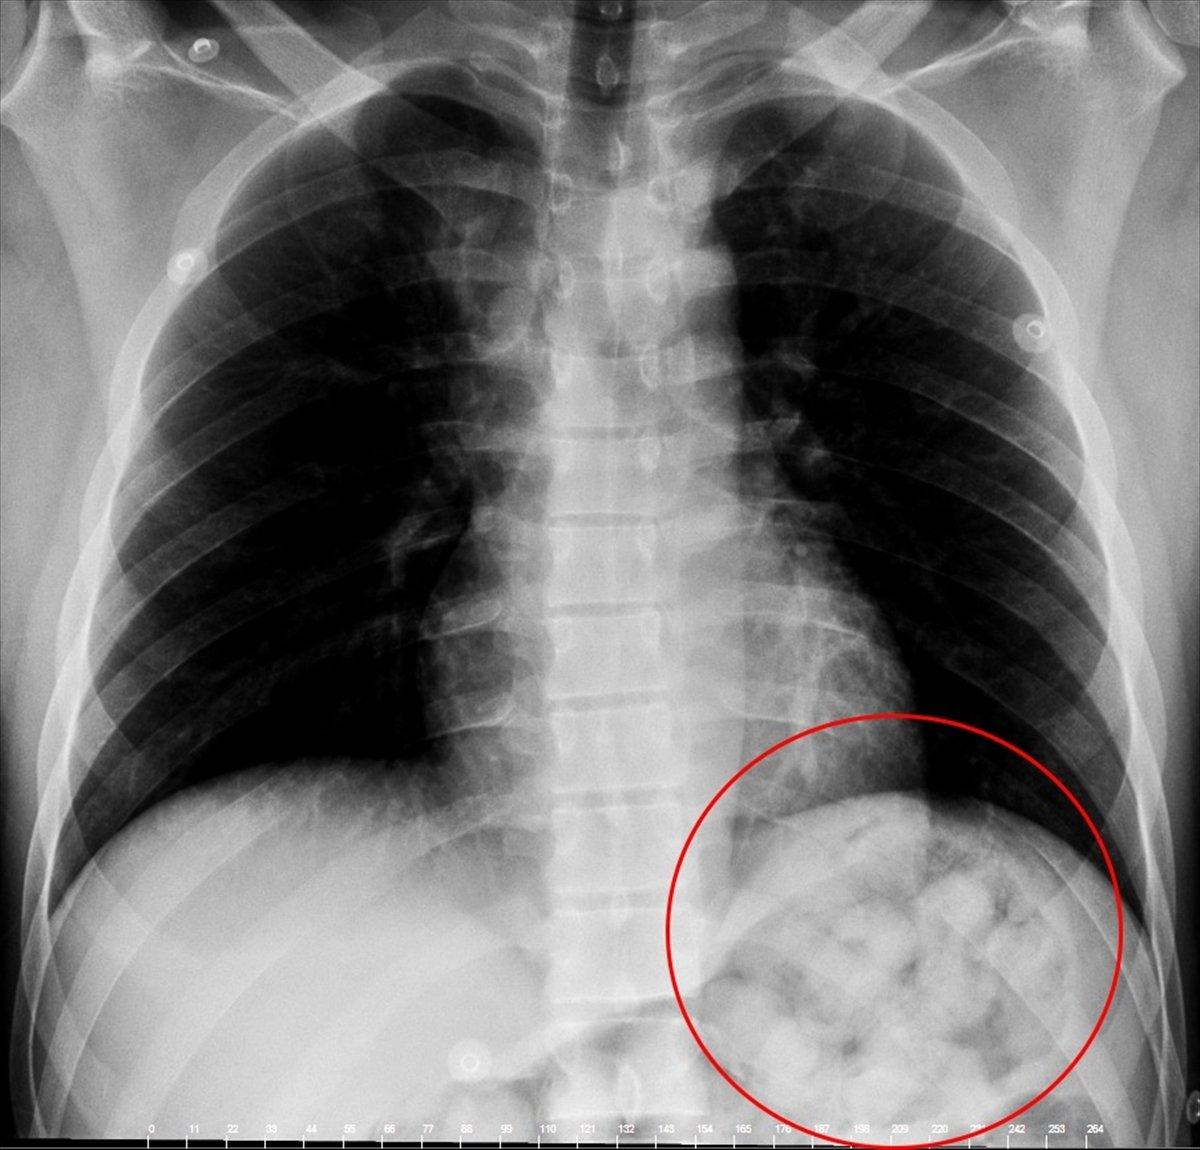

2'Sİ PATLAMIŞ 72 KAPSÜL ÇIKARILDI

Tedavi altına alınan Narziveh'in çekilen röntgen filminde midesinde cisim tespit edildi. Ameliyata alınan Zarziveh'in midesinden 2'si patlamış 72 adet kapsül halinde uyuşturucu madde çıkarıldı.